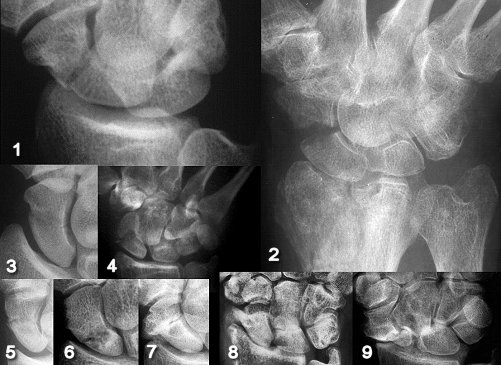

Figure Legend:

Scaphoid fractures usually occur as an isolated fracture (1) but may be

part of a larger injury complex (2). Oblique (3), comminuted (4) and

proximal (9) fracture lines are prone to nonunion. Nonunion may be

radiographically subtle (5), cystic (6) or hypertrophic (7). The

majority of scaphoid nonunions progress to a pattern of radioscaphoid

and midcarpal arthritis referred to as Scaphoid Nonunion Advanced

Collapse or "SNAC wrist" (8, 9).